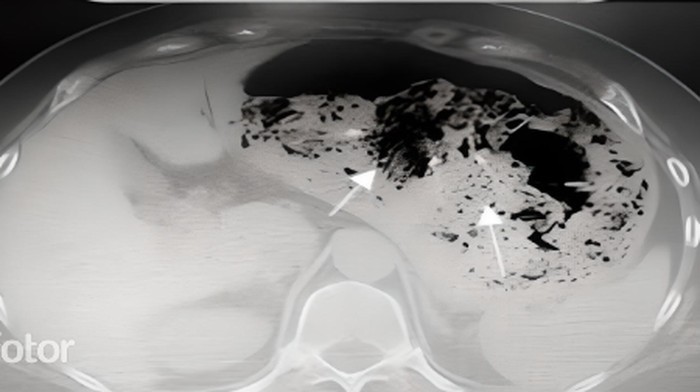

Seorang pasien perempuan 63 tahun yang tidak disebutkan dibawa ke unit gawat darurat Gongli Hospital, Shanghai, China dengan keluhan kesulitan menelan. Berdasarkan hasil CT-scan abdomen, lambun pasien sangat distensi, serta berisi gas dan benda asing debris. (Foto: Journal of Pharmacological Reports)